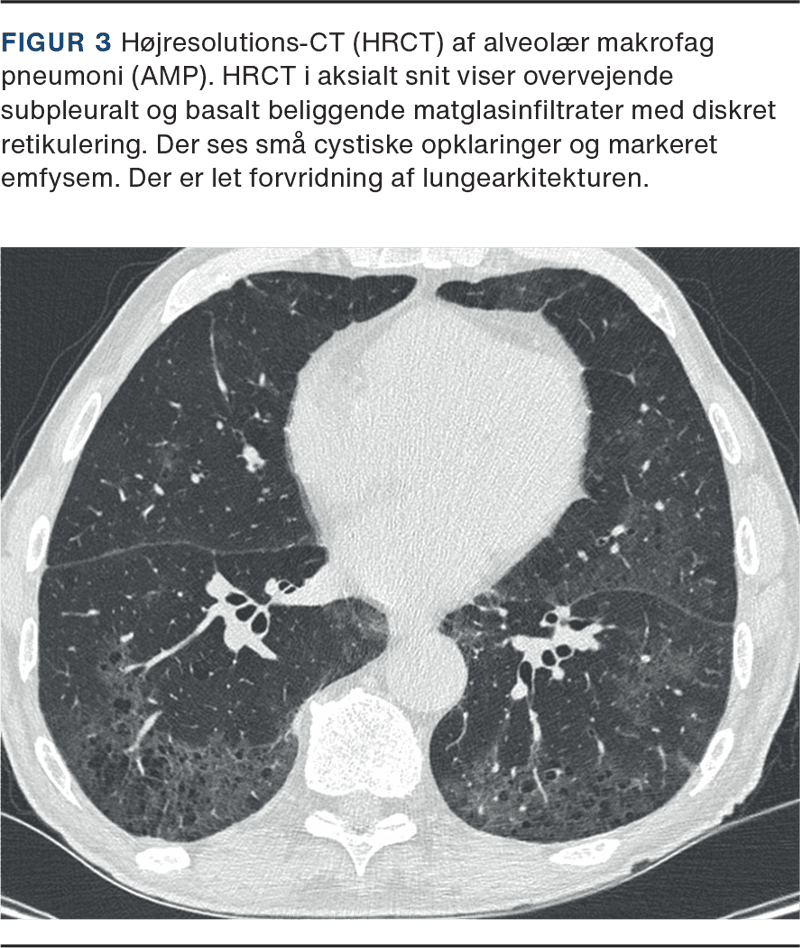

HRCT viser i tidlige stadier små, centrilobulære noduli, som over tid kan udvikle sig til uregelmæssige og tyndvæggede cyster (Figur 1 A). PLCH regnes også blandt de cystiske lungesygdomme, idet cystedannelsen udgør et centralt patoanatomisk træk. De tyndvæggede cyster er årsagen til den forhøjede forekomst af spontan pneumothorax. Disse forandringer er primært lokaliseret i midt- og overzonen, mens de basale og subpleurale områder oftest er relativt skånet [9]. Den nodulære fase kan differentialdiagnostisk give udfordringer og forveksles med maligne infiltrater, og den sencystiske fase er svær at skelne fra emfysem. Histopatologisk ses karakteristiske peribronkiolære infiltrater med ophobning af langerhanske celler (Figur 1 B), der immunhistokemisk er positive for CD1a (Figur 1 C), Langerin (CD207) (Figur 1 D) og S100. Der er ofte ledsagende eosinofile granulocytter, lymfocytter og makrofager, og destruktion af bronkiolernes væg med dannelse af afrundede eller stjerneformede noduli, der bliver tiltagende fibrotiske og kan kavitere.